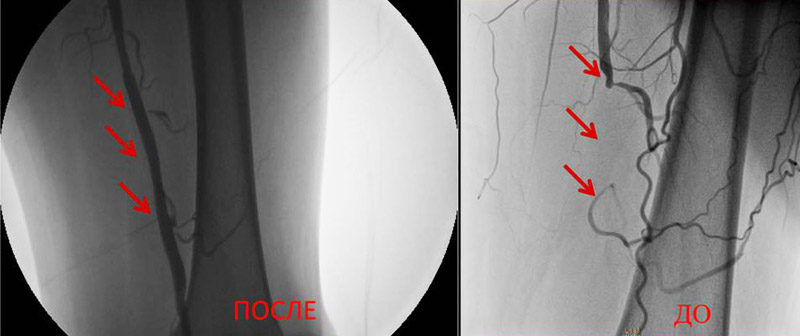

Результаты артериральных реконструкций

До и После